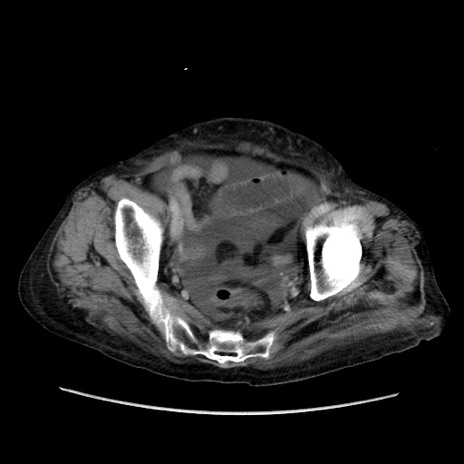

症例31(横断像)

【症例】80歳代 女性

【主訴】腹部膨満感

【現病歴】他院にて肝硬変にてフォロー中。1週間前から便秘、腹部膨満感、臍部腫瘤あり受診となる。

【既往歴】肝硬変

【身体所見】腹部膨隆あり、皮膚変化なし、疼痛なし。

【データ】WBC 4600、CRP 0.25